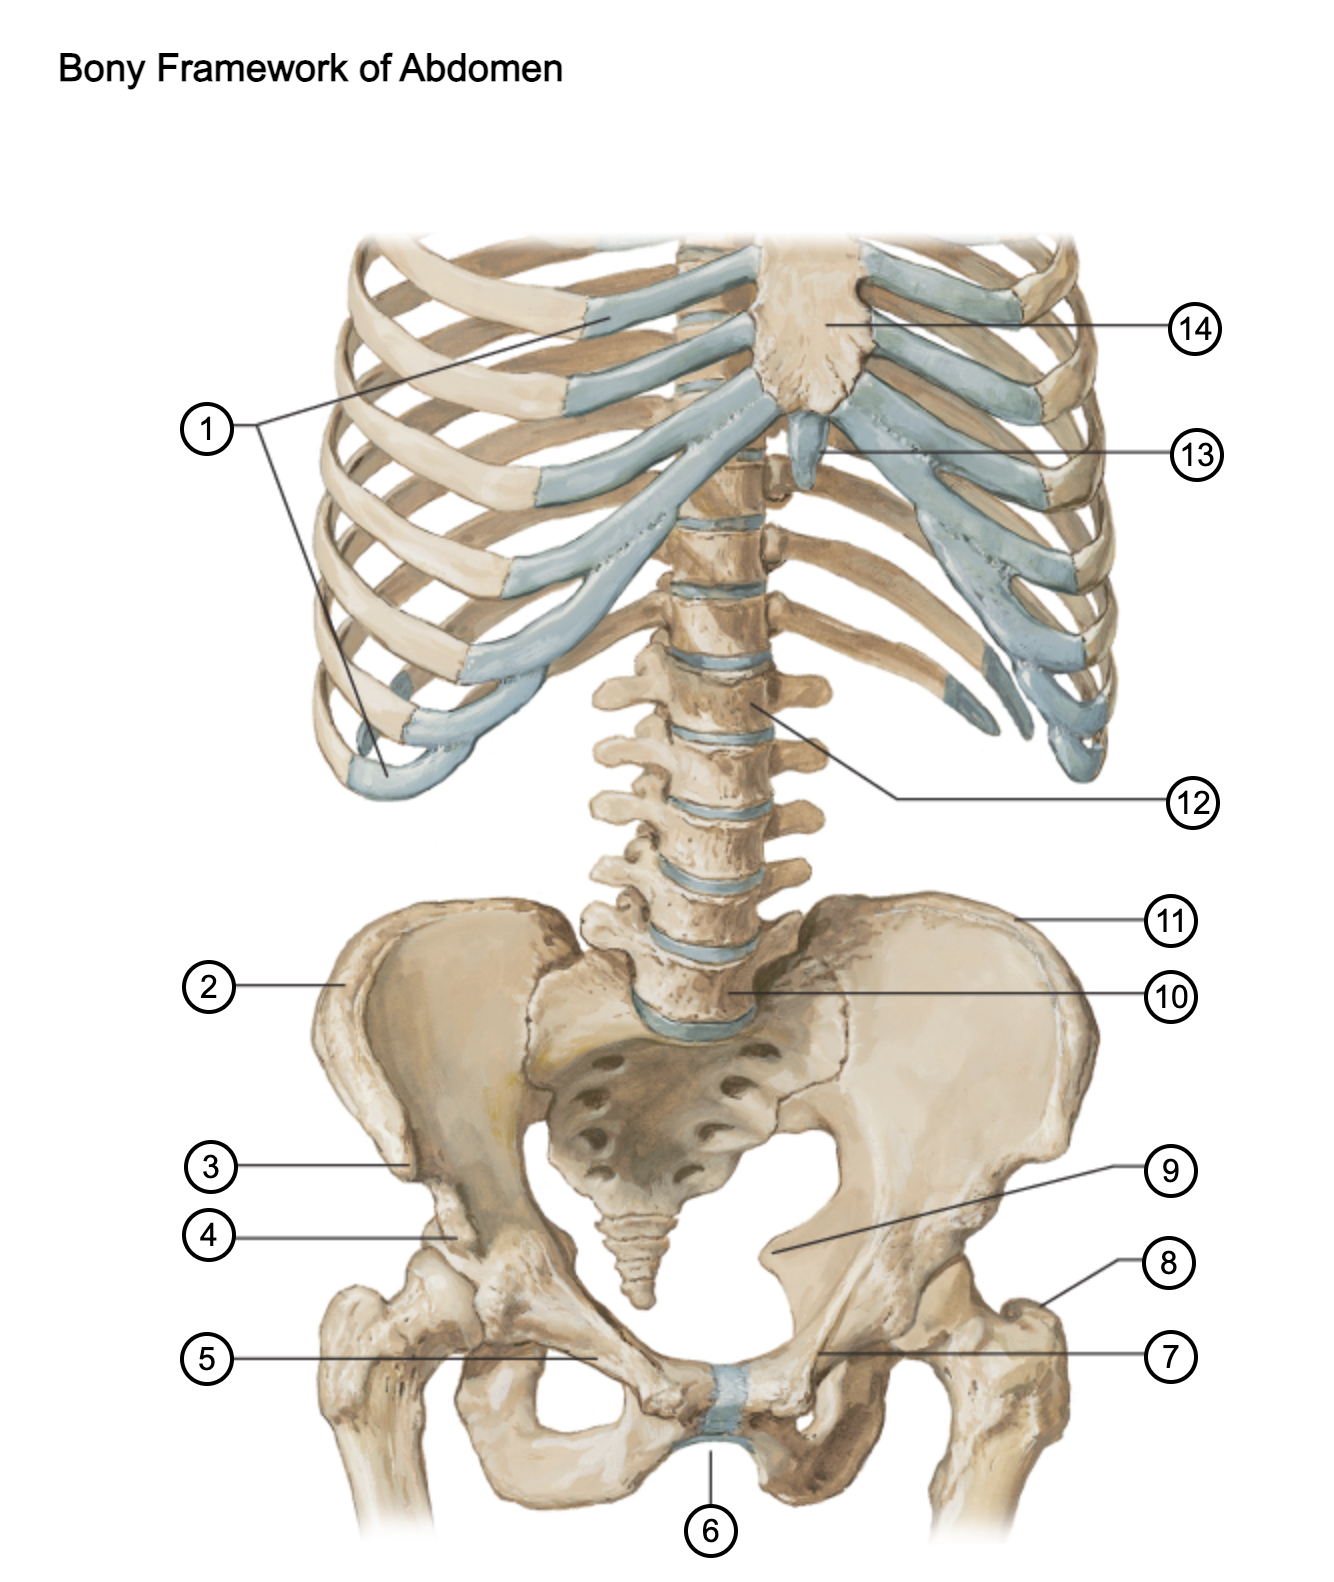

1

costal cartilages

2

iliac crest

3

anterior superior iliac spine

4

anterior inferior iliac spine

5

superior pubic ramus

6

pubic arch

7

pecten pubis

8

greater trochanter

9

ischial spine

10

L5 vertebra

11

iliac crest

12

L1 vertebra

13

xiphoid process

14

body of sternum